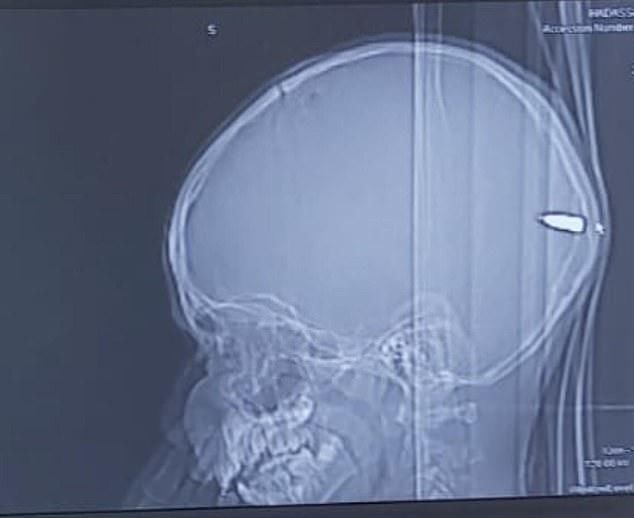

巴勒斯坦一名9岁男孩在和朋友玩耍时突然被什么东西砸了一下,随后总是昏昏欲睡,提不起精神。父母带他去了当地一家医院接受检查,不料医生竟在男孩大脑中发现了一颗子弹,立即通过手术方式取了出来。负责手术的医生盖伊·埃洛表示:“男孩能活着堪称是奇迹,幸运的是手术非常成功,男孩脱离了生命危险”。据分析,男孩中枪的原因很可能因为当地人在庆祝活动中鸣枪,男孩被流弹击中。

盖伊·埃洛是是负责这场手术的神经外科医生,他介绍道:“男孩来自东耶路撒冷,父母把他送到哈达萨医疗中心时男孩意识清醒。但我们发现他头上有一个微小的伤口。我们检查发现子弹从男孩头骨一侧进入,穿过他的大脑,在后脑勺附近停止,男孩的父母完全不知道儿子中枪了。男孩的母亲说男孩当时正在和朋友玩耍,突然说有什么东西砸到了他的头,但因为只有一个小伤口,我们都没有在意”。

男孩能活下来堪称奇迹,因为如果子弹从另一个角度射入就会对大脑造成严重伤害,并造成神经损伤,如今男孩已经脱离了危险。